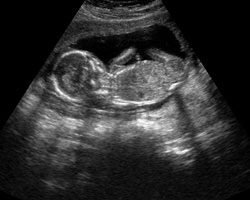

Cada vez maior e com traços mais bem definidos! Em seguida oferecemos-te um vídeo para que possas er o feto em movimento na 15ª semana, além da ecografia correspondente a esta semana. Não percas!

Ecografia 15 semanas